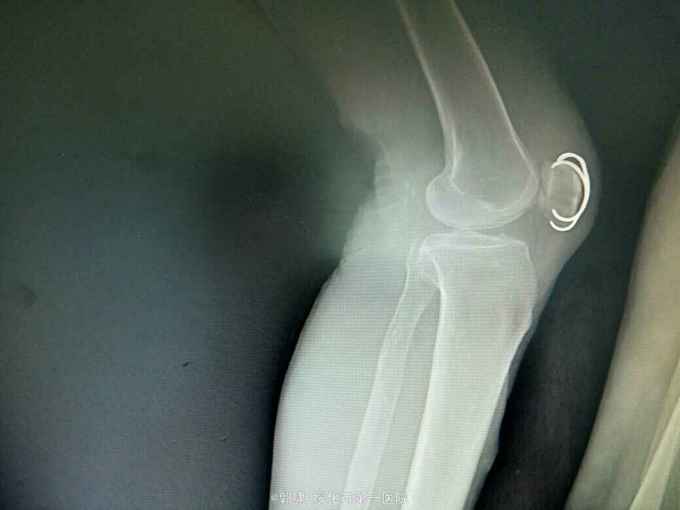

左膝关节摔伤,肿胀,畸形,活动受限一小时。收入院。患者于一小时前滑倒摔伤。当即倒地,左膝关节肿胀,畸形不能行走。门诊拍片示:左膝关节髌骨骨折,断端移位。门诊以左髌骨骨折收入院。

左膝关节肿胀,局部畸形,不能下地行走。浮髌试验阳性。拍片示:左髌骨骨折。

诊断:左髌骨骨折。立即予以腰麻下行切开复位内固定术。术中复位骨折,缝合筋膜,冰水浸泡髌骨爪约10分钟。待髌骨爪变软。选取合适大小的髌骨爪。应用记忆合金髌骨爪内固定。立即用40°温盐水热敷局部。使记忆合金加速抓紧。环抱。缝合爪齿二道,防止脱落。缝合关节囊,韧带组织。术毕。

应用记忆合金髌骨爪内固定髌骨骨折。手术时间基本在20----30分钟内都可以完成。局部损伤小。固定牢靠,确实。患者二个月就可以下地负重活动。具体手术技巧。一是髌骨爪提前用冰盐水侵泡10分钟左右。待记忆合金变软即可使用。二。固定牢靠后立即用40°温盐水热敷。使其快速抓紧。三,缝合爪齿,防脱。四如有粉碎,小的骨块可以缝合筋膜固定。有大骨块,最好环扎钢丝,或穿针固定,有时穿骨隧道钢丝捆扎。效果也不错。只要做到以上几点。安全无忧了!以下是以前做的片子。可以看一看。